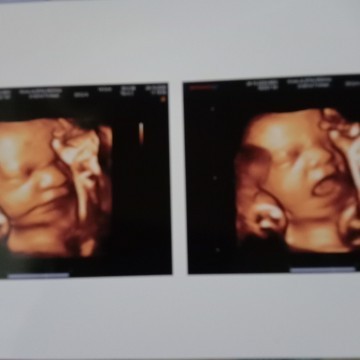

35wk .. ga sabarrrr pengen cepet ketemuu... gemessss

waktu 27 minggu, masyaAllah terlalu gemes🥰

38week, baby girl 😍 Dede nya manyun 🤭

Kemaren usg si bayi lgi nguap bun 😆